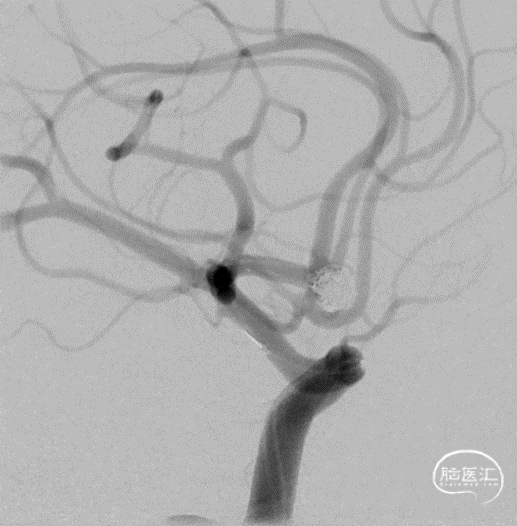

术后正侧位片 动脉瘤完全不显影,双侧A2显影均良好;术后下撤Heralder®DA远端通路导引导管再行颈内动脉造影显示颈内动脉全程无痉挛,提示Heralder®DA远端通路导引导管对颈内动脉的刺激小,无损伤。